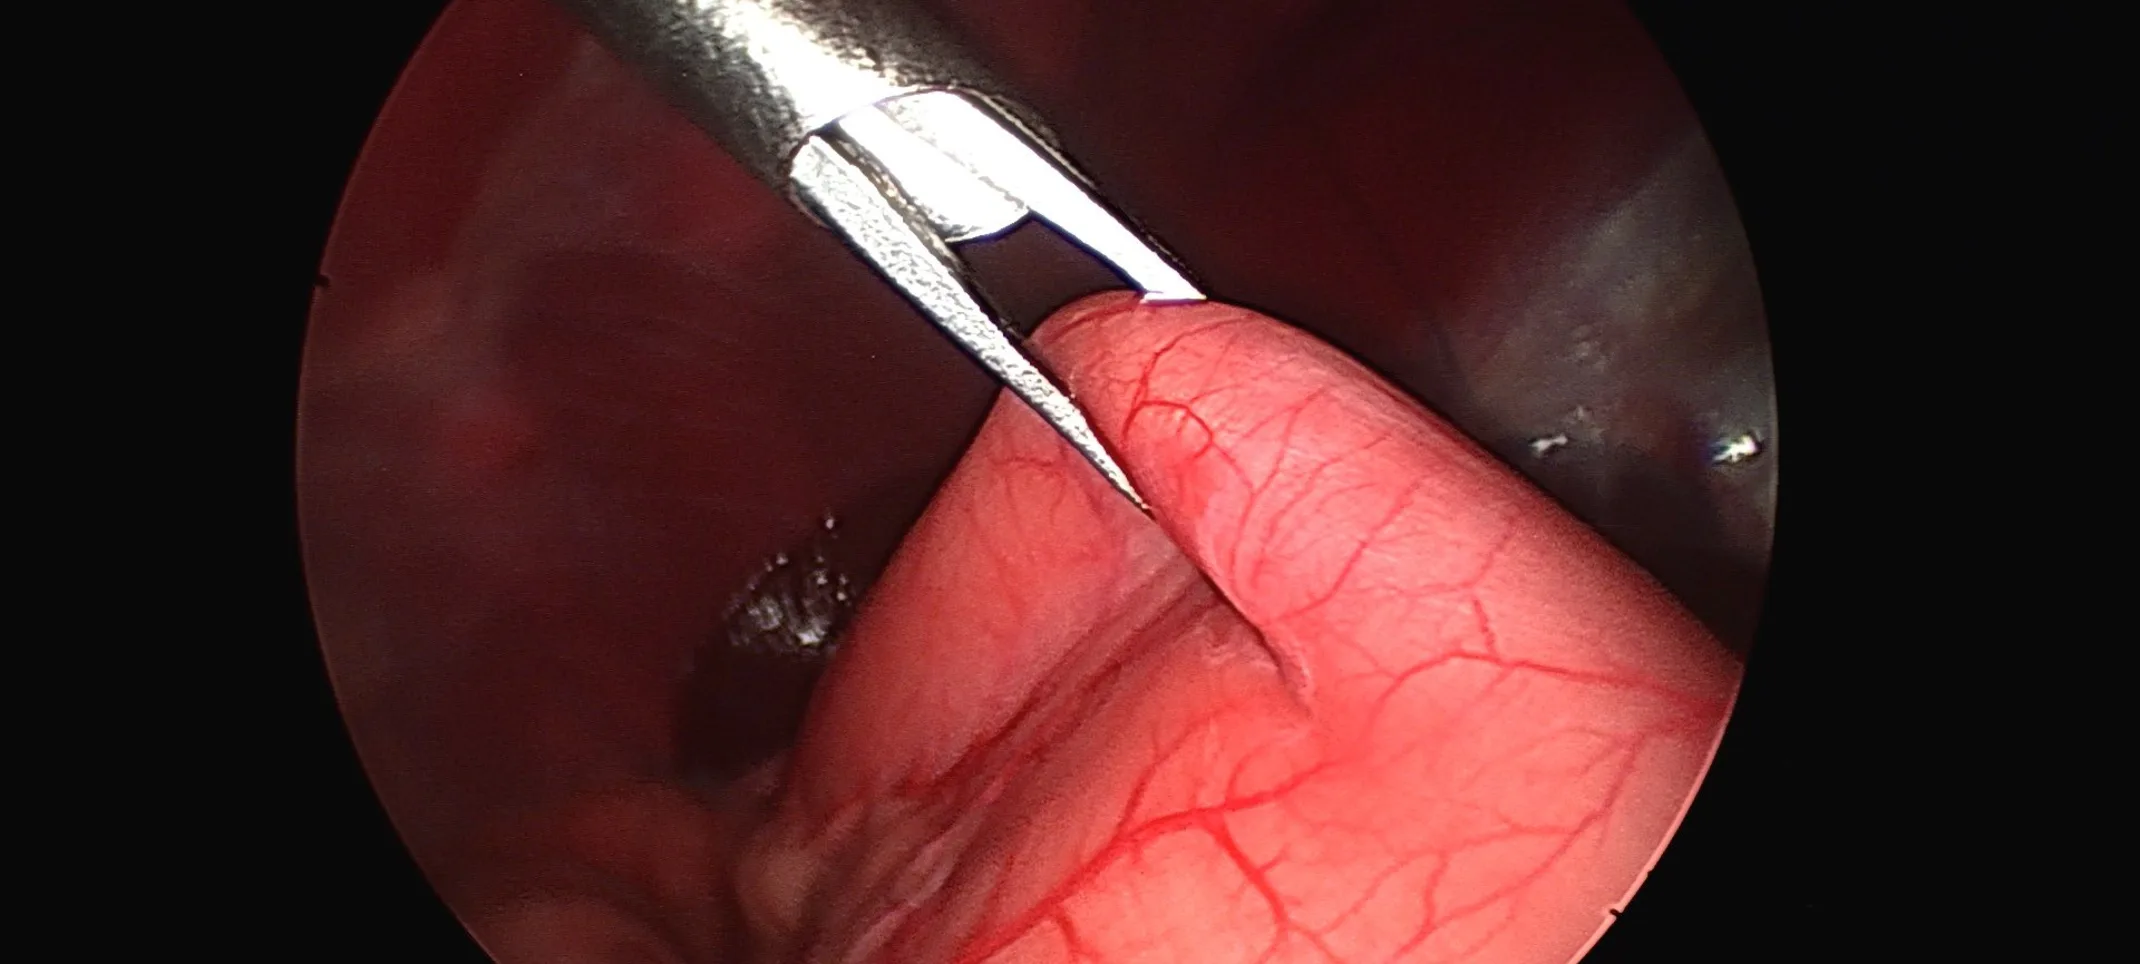

Appearance of the stomach being grasped by forceps to be sutured to the abdominal wall